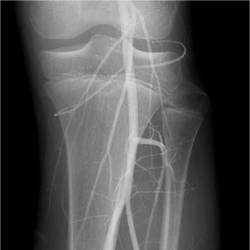

Gallery of Unlabled Radiographs from Lecture (Dr. French) - 2020

Click a thumbnail to enter the gallery display. Click the file name link at the bottom left of the gallery display to view the image at high resolution.

Labeled Plates from Lecture (Dr. French) - 2020

RadiologyLowerLimbThoraxQuestionPoolLabeled_01_2020.pdf

Click right side of plate to step forward or left side of plate to step backward.